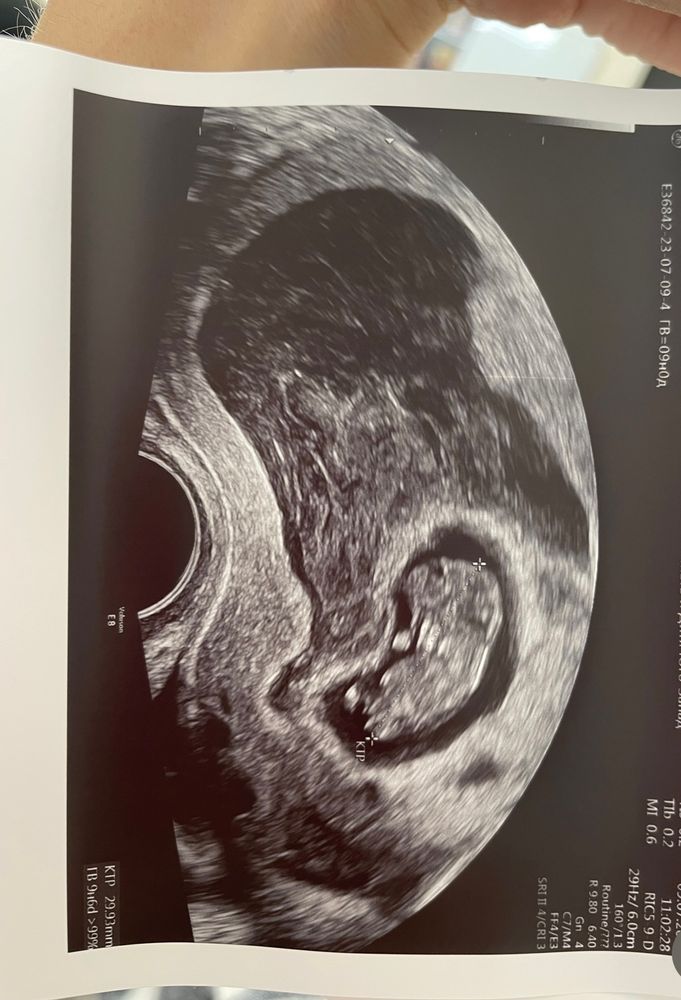

Вот моя , не рассосалась. Вышла в родах на плаценте. тут размеры где-то 80/60/55… огромная. И срок тут меньше вашего , малыш тут вообще прижат в уголке этой гематомой. Оба раза так было, оба раза обошлось Изображение